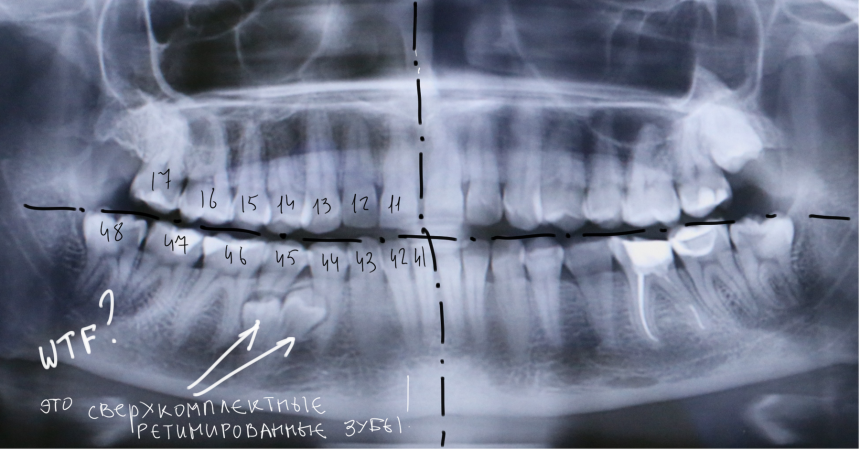

У моей пациентки случайно мы обнаружили два ретинированных сверхкомплектных премоляра:

При этом, весь комплект зубов на месте (за исключением правой верхней восьмерки — моя работа).

Вот разбор снимка:

Давайте еще раз посмотрим на снимок:

Что мы на нем видим? Ну да, есть два лишних зуба.